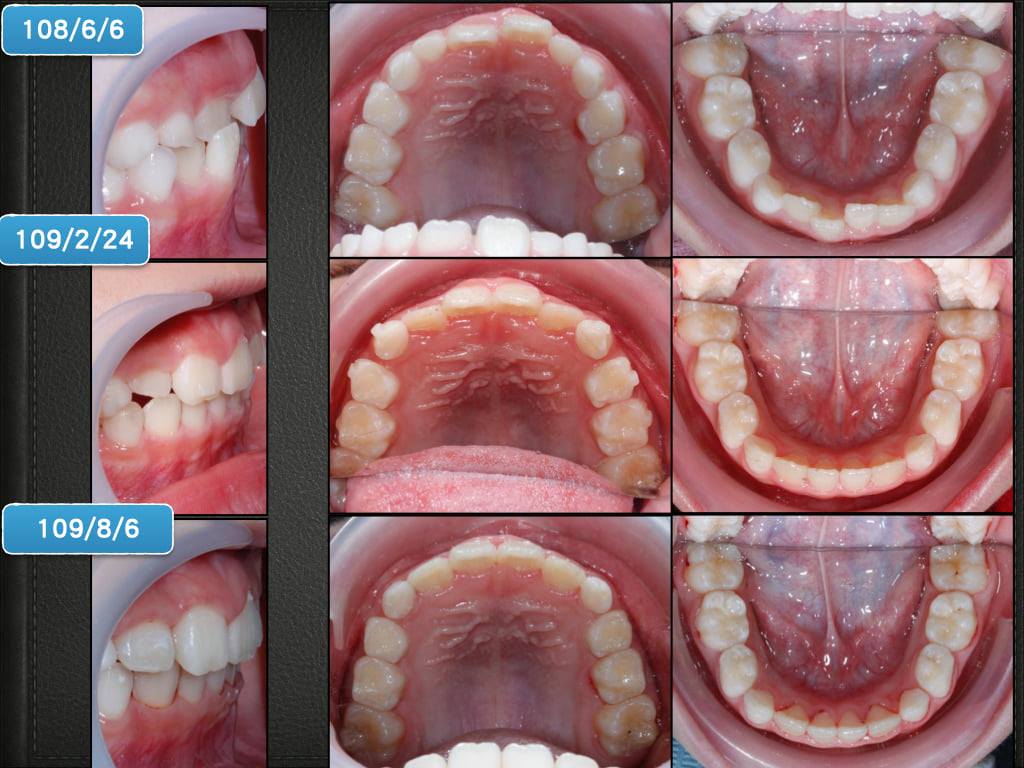

案例分享『17』--- 前牙錯咬之混合齒列矯正

至少下顎恆門牙4顆,上顎恆門牙2顆長出:這個時候小病患較聽得懂話,也比較願意配合治療,這種第一階段的矯正,目標是把上下門牙4顆排整齊,並創造足夠的空間,讓未來的牙齒可自然萌發排整齊,大家要有一個觀念,牙齒會排不整齊,就是因為空間不夠!!隱適美-first可以連乳牙一起移動,並提供更多的空間,讓未來萌發的牙齒有更多的空間!那透過1年多的治療,大部分的病例都可以達到很好的成果。再來就是等待換牙,那因為青春期的變數真的很大,有些案例的確需要在高中或大學時再做一次矯正,但只要空間留得夠,未來成人矯正的機率可以大大降低,就算真的需要再矯正,難度也會降低很多!